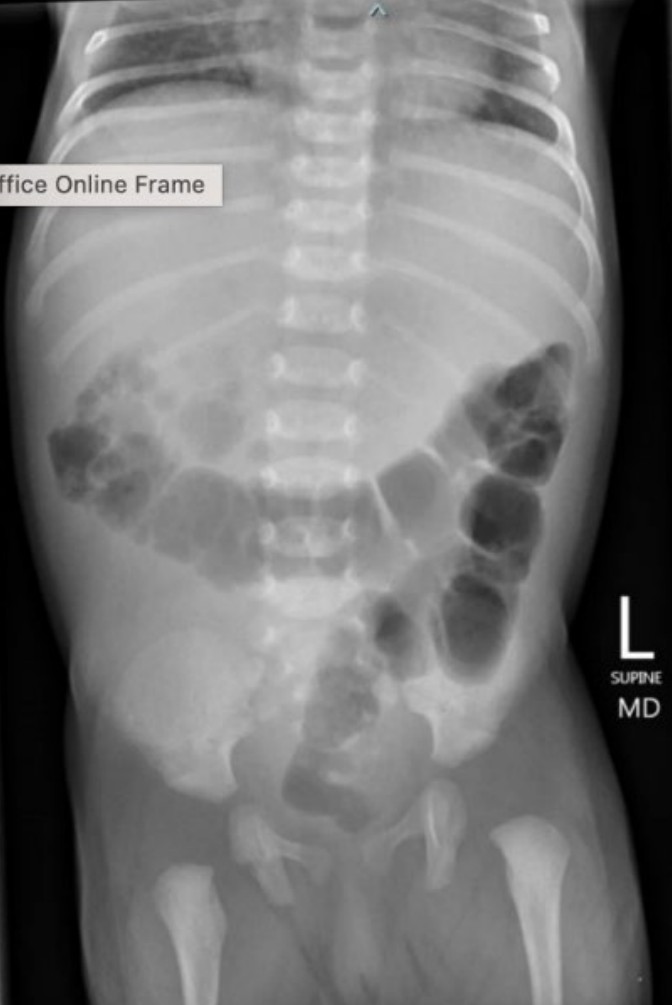

Abdominal pain

A 65-year-old man presents with central abdominal pain radiating to the back, associated with nausea and vomiting. He appears unwell. …